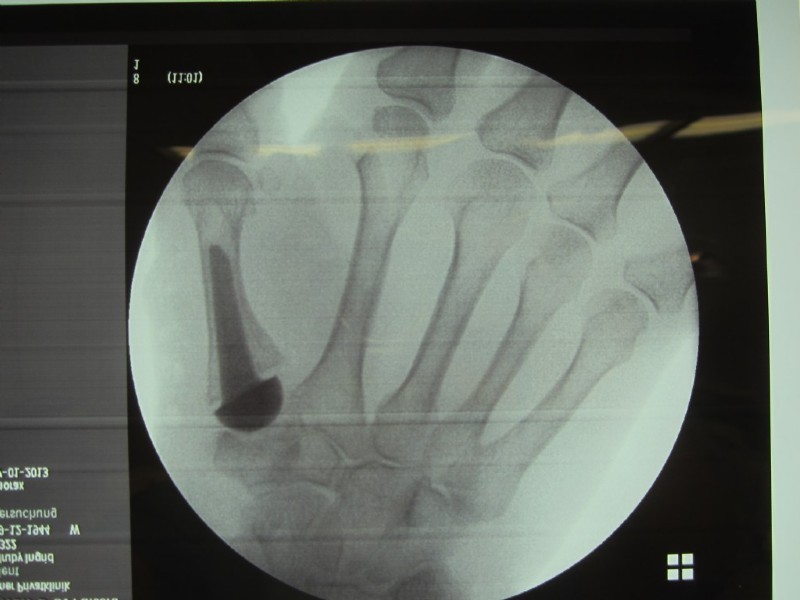

Finger-end joint stiffening and middle joint replacement in rheumatoid patients.

Left: Red Arrow: Horn-like deposits as an sign of osteoarthritis, yellow arrow: complete destruction of the joints, with inflammation and pain at rest and at work.

Middle and right: stiffening in the functional position with the V-tek regular screw. Eliminates pain and visually shows a satisfying result.

Below: End-joint stiffening in the index finger and middle-joint endoprosthesis in the middle finger